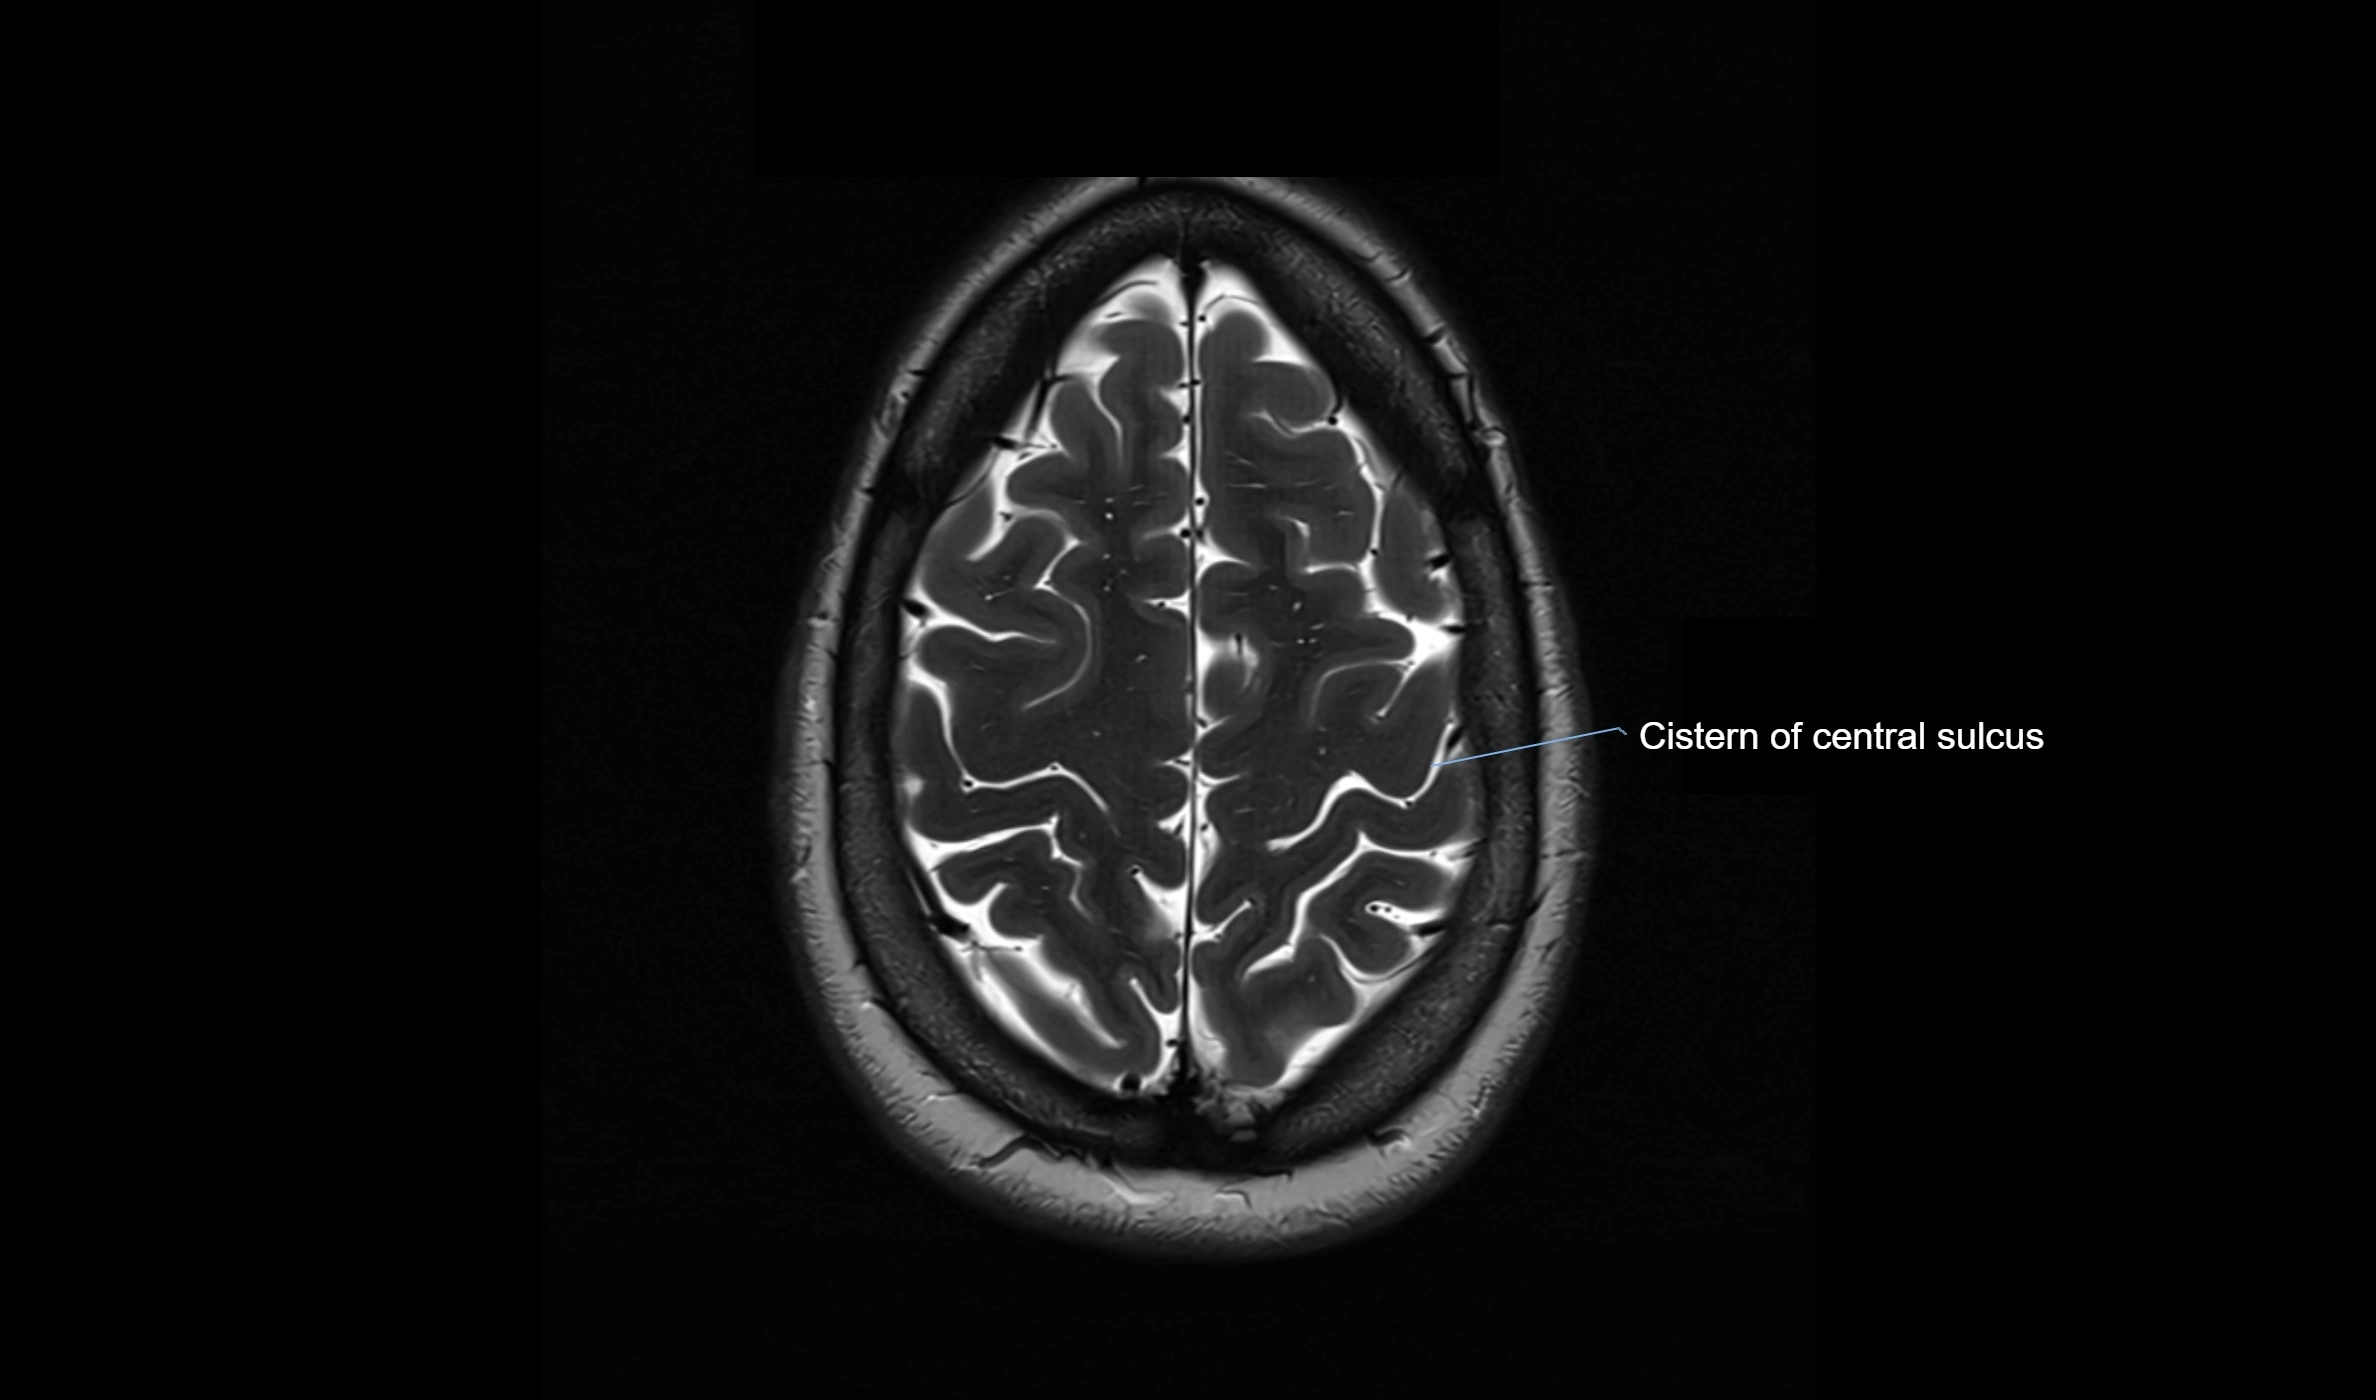

CT image

image